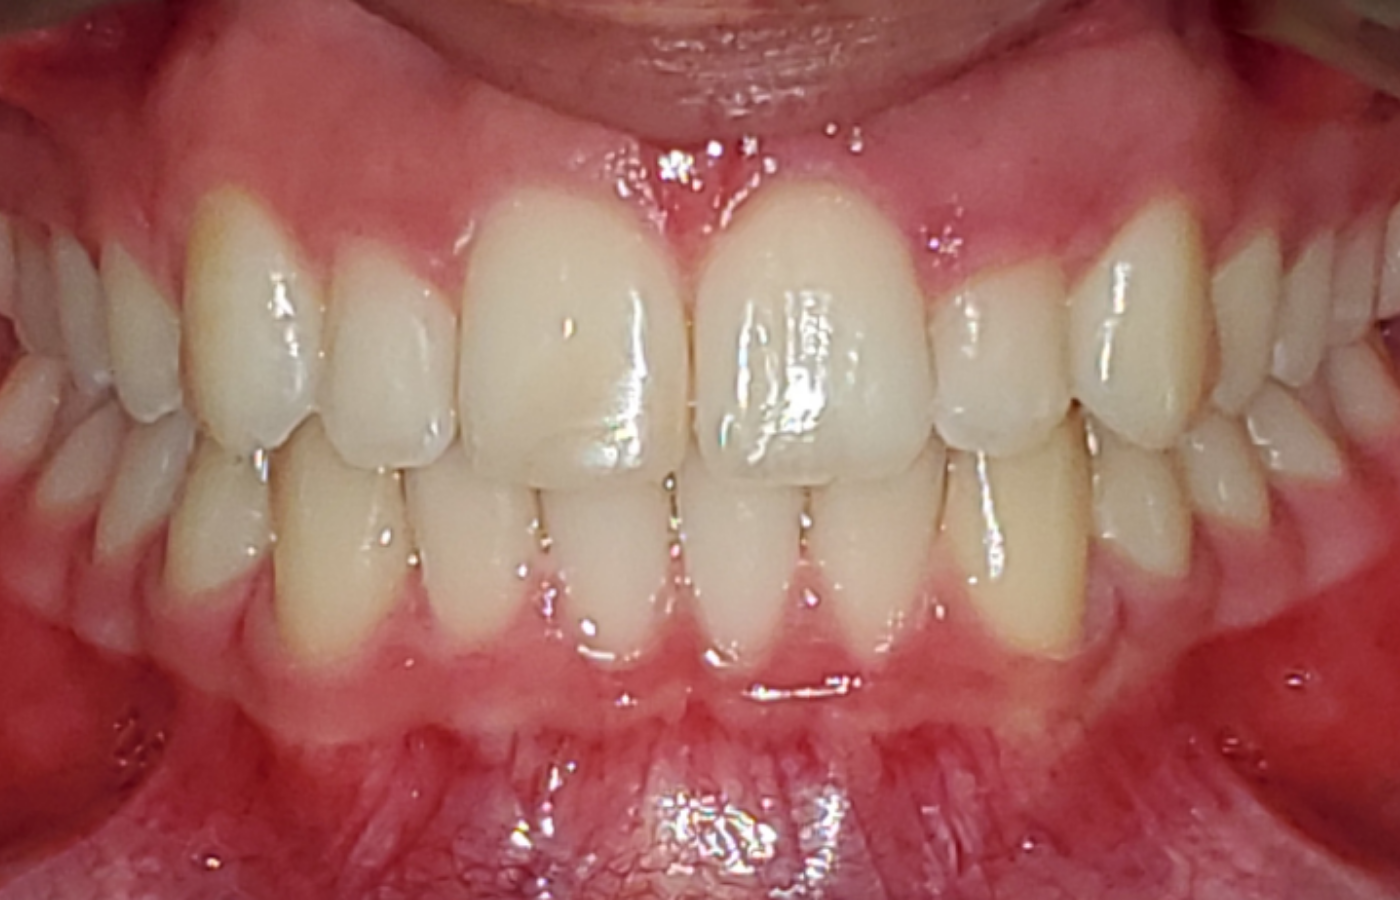

After that small delay, the case progressed as planned, and the patient completed her 16-aligner series just a few weeks later. She returned to Willow Family Dentistry satisfied with her results.

“I can’t believe how fast it worked,” says the patient. “I’m actually smiling with my teeth now, and I can eat without worrying about biting my lip. It’s a huge relief.”

“Her occlusion is vastly improved, they no longer have issues chewing, and they feel more confident in the look of their smile,” says Dr. Jeong.

Over the course of 7 months, Dr. Jeong was able to expand this patient’s arch forms via dental tipping, close residual spacing from arch development, correct rotations and crowding, un-trap her mandibular arch via overbite correction, improve her overjet and midlines, improve her tongue positioning, and resolve her anterior crossbite.

Under the direction of Dr. Jeong, this patient is seeing improvements to her comfort and confidence—she’s also improved her long-term health. With a healthier occlusion, she faces a reduced risk of chipping, cracking, abfractions, and even hygiene-related concerns.